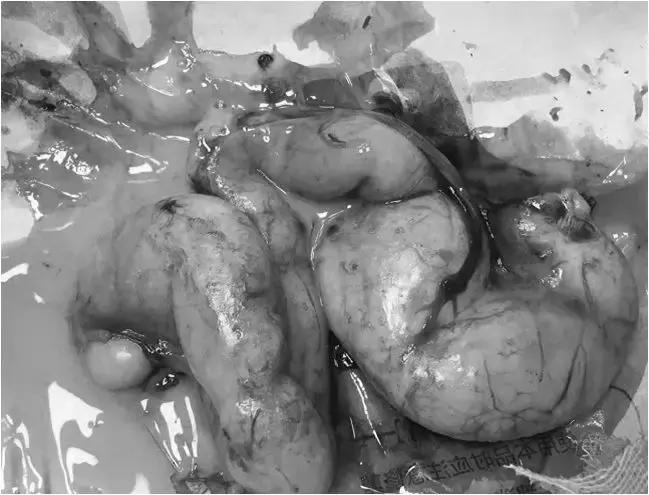

除此之外还进行外科手术

将已感染的卵巢和子宫一并切除